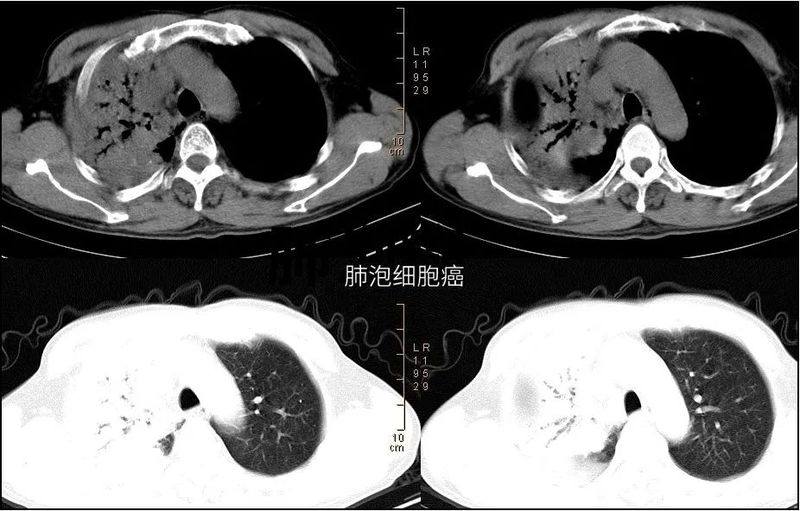

Ⅲ型支气管造影征(枯树枝征):

在肺大片实变阴影中,有较大的充气支气管影像,而较小的支气管不显影,支气管管壁不规整,凹凸不平,广泛性狭窄、僵硬、扭曲。该征和肺炎中的充气支气管不同的是小支气管不显影,充气的大支气管管壁不规整,凹凸不平,广泛性狭窄、僵硬、扭曲,走形不自然。该征象是肺泡癌的特征性表现,无论从发病机制和影像表现都和肺炎的充气支气管征有本质的区别。

临床意义:充气支气管征的最常见原因是肺炎和肺泡型肺水肿。合并肺不张时,提示支气管在其开口处并未阻塞。间质纤维化和某些肿瘤也可产生空气支气管征。虽然肿瘤往往是实性肿块,但淋巴瘤和细支气管肺泡癌的特征也与空气支气管征相关。